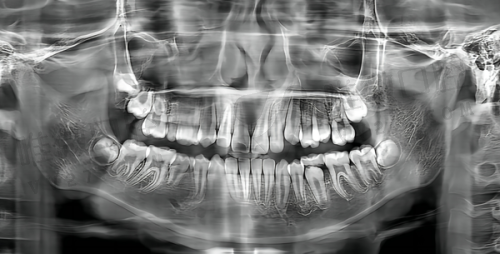

数字化种植技术

:配备CBCT、口扫仪等设备,实现精细种植

牙齿种植

- 常规种植

- 即刻种植

- 数字化导板种植

- All-on-4/6全口种植

- 骨增量手术